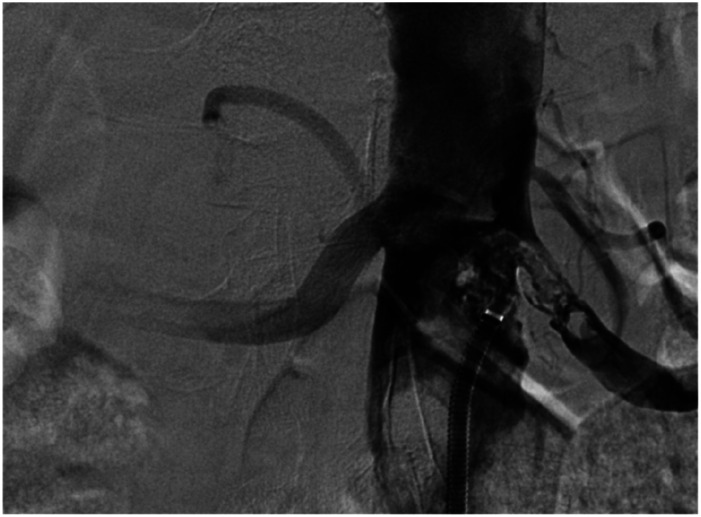

摘要:原发性主动脉恶性肿瘤是一种非常罕见的病理,迄今为止文献中仅报道了190例主动脉肿瘤。通常,症状是隐匿的和非特异性的,所以这种疾病在晚期才被诊断出来。目的:在此,我们报告一例原发性主动脉恶性肿瘤。在我们的病例中,诊断是通过计算机断层血管造影(CTA)和在主动脉造影中获得的不确定肿块的活检来建立的。方法:患者手术切除病变主动脉段并合并肿瘤。组织病理检查显示为原发性主动脉恶性肿瘤-血管肉瘤。术后患者按肉瘤标准治疗方案接受辅助化疗。结果:术后1个月行胸腹骨盆CT检查,未见病灶转移及病理淋巴结。结论:手术联合全身治疗可提高总生存率。

Introduction: Primary aortic malignancy is a very rare pathology, with only 190 cases of aortic tumors reported in the literature to date. Usually, symptoms are insidious and nonspecific, so the disease is diagnosed at an advanced stage. Objective: Here, we present a case report of a primary malignant tumor of the aorta. In our case, the diagnosis was established using computed tomography angiography (CTA) and biopsy of indeterminate masses obtained during aortography. Methods: The patient underwent surgical resection of the affected aortic segment along with a tumor. Histopathological examination revealed the diagnosis of a primary malignant tumor of the aorta - angiosarcoma. Postoperatively, patient received adjuvant chemotherapy according to the standard treatment regimen for sarcoma. Results: One month later, postoperative CT of a chest, abdomen and pelvis was performed, revealing no evidence of metastases or pathological lymph nodes in the examined areas. Conclusion: Combined surgical and systemic therapies may improve overall survival.